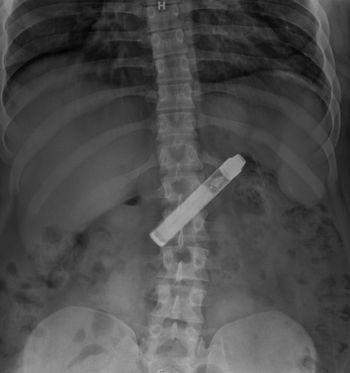

What foreign body did the patient ingest?